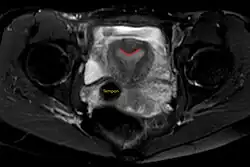

Arcuate uterus (marked in red) seen on MRI